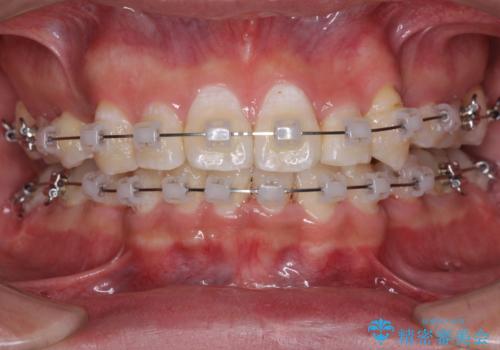

- クリアブラケット

- 3年3ヶ月

- 10-30回

奥歯の咬み合わせを改善したいため、治療期間が長くなりましたが、患者様には辛抱強くお付き合いいただきました。

上下の正中を合わせることもでき、患者様には大変満足していただきました。